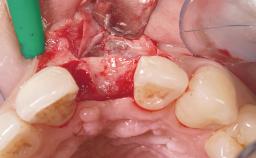

Immediate Flapless Placement of an Implant in a Maxillary Left Central Incisor Site

A 42-year-old female patient was referred to our clinic at the School of Dentistry of the University of São Paulo in November 2004, presenting a deficient restoration in the upper left central incisor. The clinical examination revealed no gingival retraction or any signs of gingival inflammation and, therefore, previous periodontal treatment was not considered. The patient presented a high lip line at full smile and a thin tissue biotype. This combination characterized a high-risk situation from an anatomic point of view, which required careful preoperative planning and cautious surgical execution.